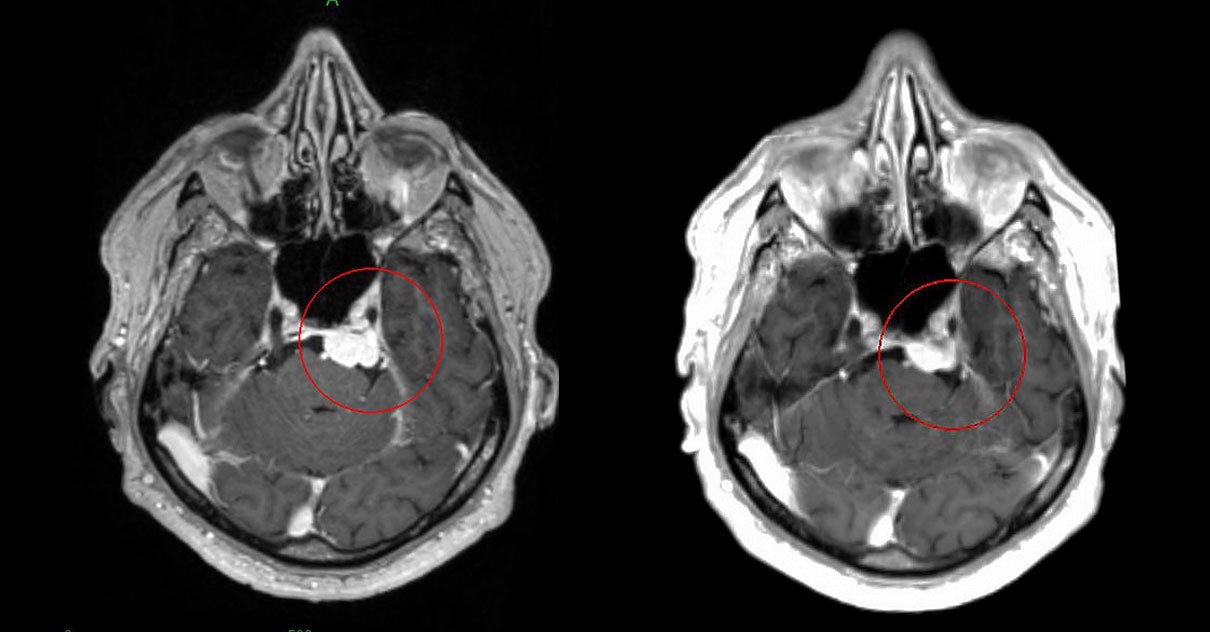

Вот изображение, иллюстрирующее процесс радиохирургии Гамма-нож при лечении менингиомы

(до и после лечения — наглядный пример уменьшения опухоли)